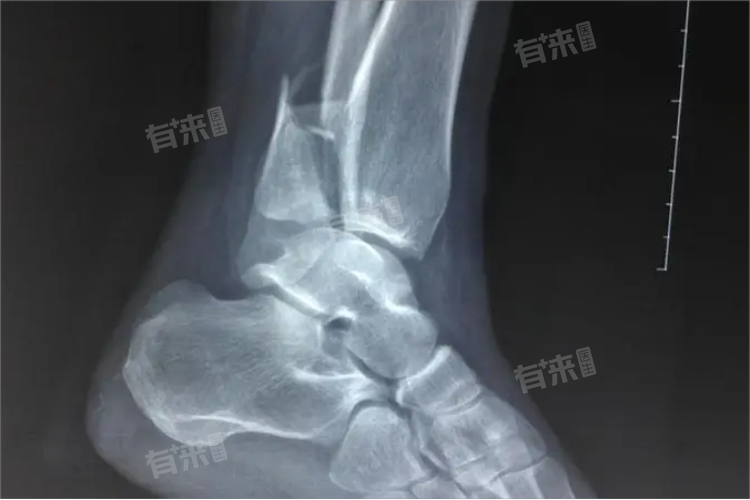

脚踝骨折指的是构成踝关节的骨骼,如胫骨远端、腓骨远端、距骨,由于直接暴力或间接暴力导致骨的连续性和完整性遭到破坏。治疗脚踝骨折的方法主要有保守治疗、手术治疗等。